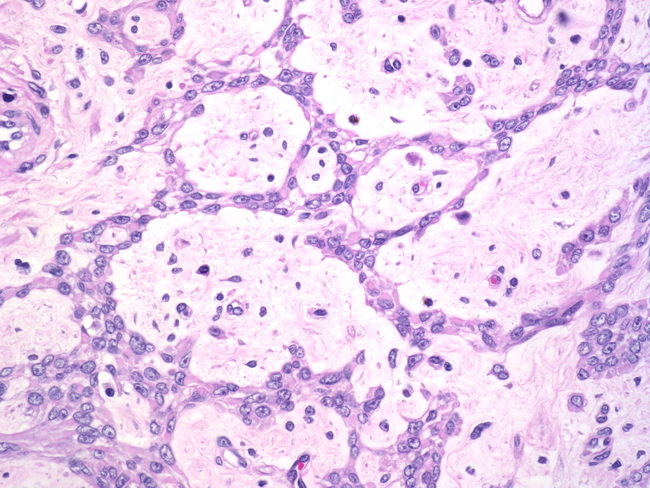

Webpathology.com: A Collection Of Surgical Pathology Images

leiomyoma myxoid change pathology webpathology comments

Webpathology.com: A Collection Of Surgical Pathology Images

uterus myxoid leiomyoma muscle smooth webpathology pathology fibrillary cells nuclei comments